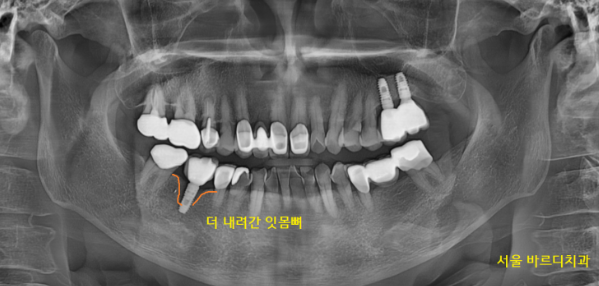

230116

원장님 치료받던 곳이

계속 붓고 아파요

드디어 올게 와버렸습니다.

임플란트 수명이 다했네요..

계속 관리하시면서 쓰셨어도

한번 무너진 잇몸뼈는 회복할 수 없습니다.

브레이크만 밟아주는 역할이지

다시 녹은 잇몸뼈가 채워지거나 하지 않거든요~~

임플란트 염증으로 잇몸뼈가 많이 녹았습니다.

4년 전과 비교해 보면 잇몸뼈가 더 많이 녹은 것이

보이실 겁니다.